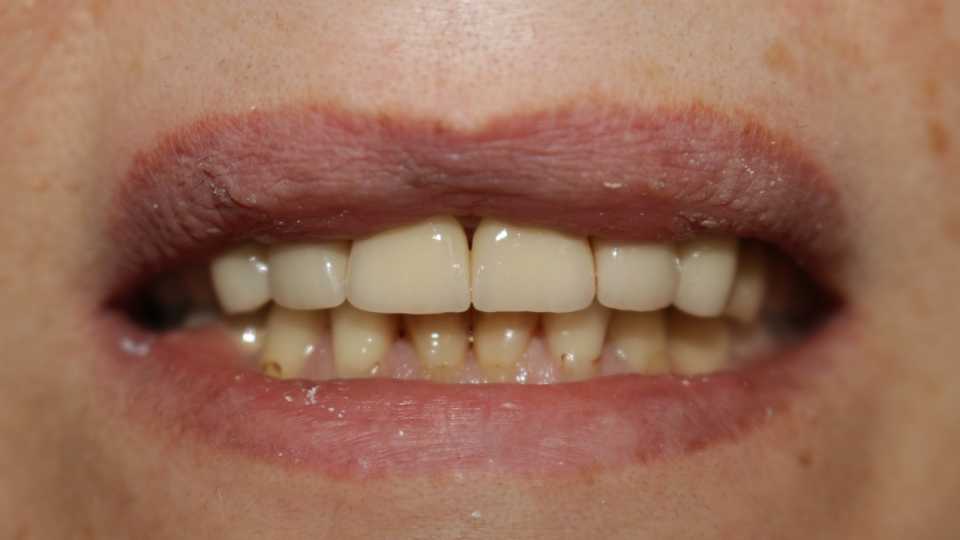

Pacienta s-a prezentat in cabinet cu intentia de a-si îmbunătăți estetica.

Poza inițială relevă obturatii nefizionomice, cu un compozit imbatranit ce prezinta la interfata cu dintele discromii exogene. De mentionat este si faptul ca toti dintii sunt vitali.